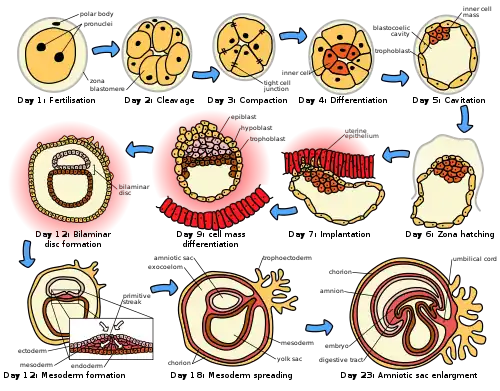

Through an interplay of hormones that includes follicle stimulating hormone that stimulates folliculogenesis and oogenesis creates a mature egg cell, the female gamete. Fertilization is the event where the egg cell fuses with the male gamete, spermatozoon. After the point of fertilization, the fused product of the female and male gamete is referred to as a zygote or fertilized egg. The fusion of female and male gametes usually occurs following the act of sexual intercourse. Pregnancy rates for sexual intercourse are highest during the menstrual cycle time from some 5 days before until 1 to 2 days after ovulation.[35] Fertilization can also occur by assisted reproductive technology such as artificial insemination and in vitro fertilisation.

Fertilization (conception) is sometimes used as the initiation of pregnancy, with the derived age being termed fertilization age. Fertilization usually occurs about two weeks before the next expected menstrual period.

A third point in time is also considered by some people to be the true beginning of a pregnancy: This is time of implantation, when the future fetus attaches to the lining of the uterus. This is about a week to ten days after fertilization.[36]

Development of embryo and fetus

The sperm and the egg cell, which has been released from one of the female's two ovaries, unite in one of the two fallopian tubes. The fertilized egg, known as a zygote, then moves toward the uterus, a journey that can take up to a week to complete. Cell division begins approximately 24 to 36 hours after the female and male cells unite. Cell division continues at a rapid rate and the cells then develop into what is known as a blastocyst. The blastocyst arrives at the uterus and attaches to the uterine wall, a process known as implantation.

The development of the mass of cells that will become the infant is called embryogenesis during the first approximately ten weeks of gestation. During this time, cells begin to differentiate into the various body systems. The basic outlines of the organ, body, and nervous systems are established. By the end of the embryonic stage, the beginnings of features such as fingers, eyes, mouth, and ears become visible. Also during this time, there is development of structures important to the support of the embryo, including the placenta and umbilical cord. The placenta connects the developing embryo to the uterine wall to allow nutrient uptake, waste elimination, and gas exchange via the mother's blood supply. The umbilical cord is the connecting cord from the embryo or fetus to the placenta.

After about ten weeks of gestational age – which is the same as eight weeks after conception – the embryo becomes known as a fetus.[37] At the beginning of the fetal stage, the risk of miscarriage decreases sharply.[38] At this stage, a fetus is about 30 mm (1.2 inches) in length, the heartbeat is seen via ultrasound, and the fetus makes involuntary motions.[39] During continued fetal development, the early body systems, and structures that were established in the embryonic stage continue to develop. Sex organs begin to appear during the third month of gestation. The fetus continues to grow in both weight and length, although the majority of the physical growth occurs in the last weeks of pregnancy.